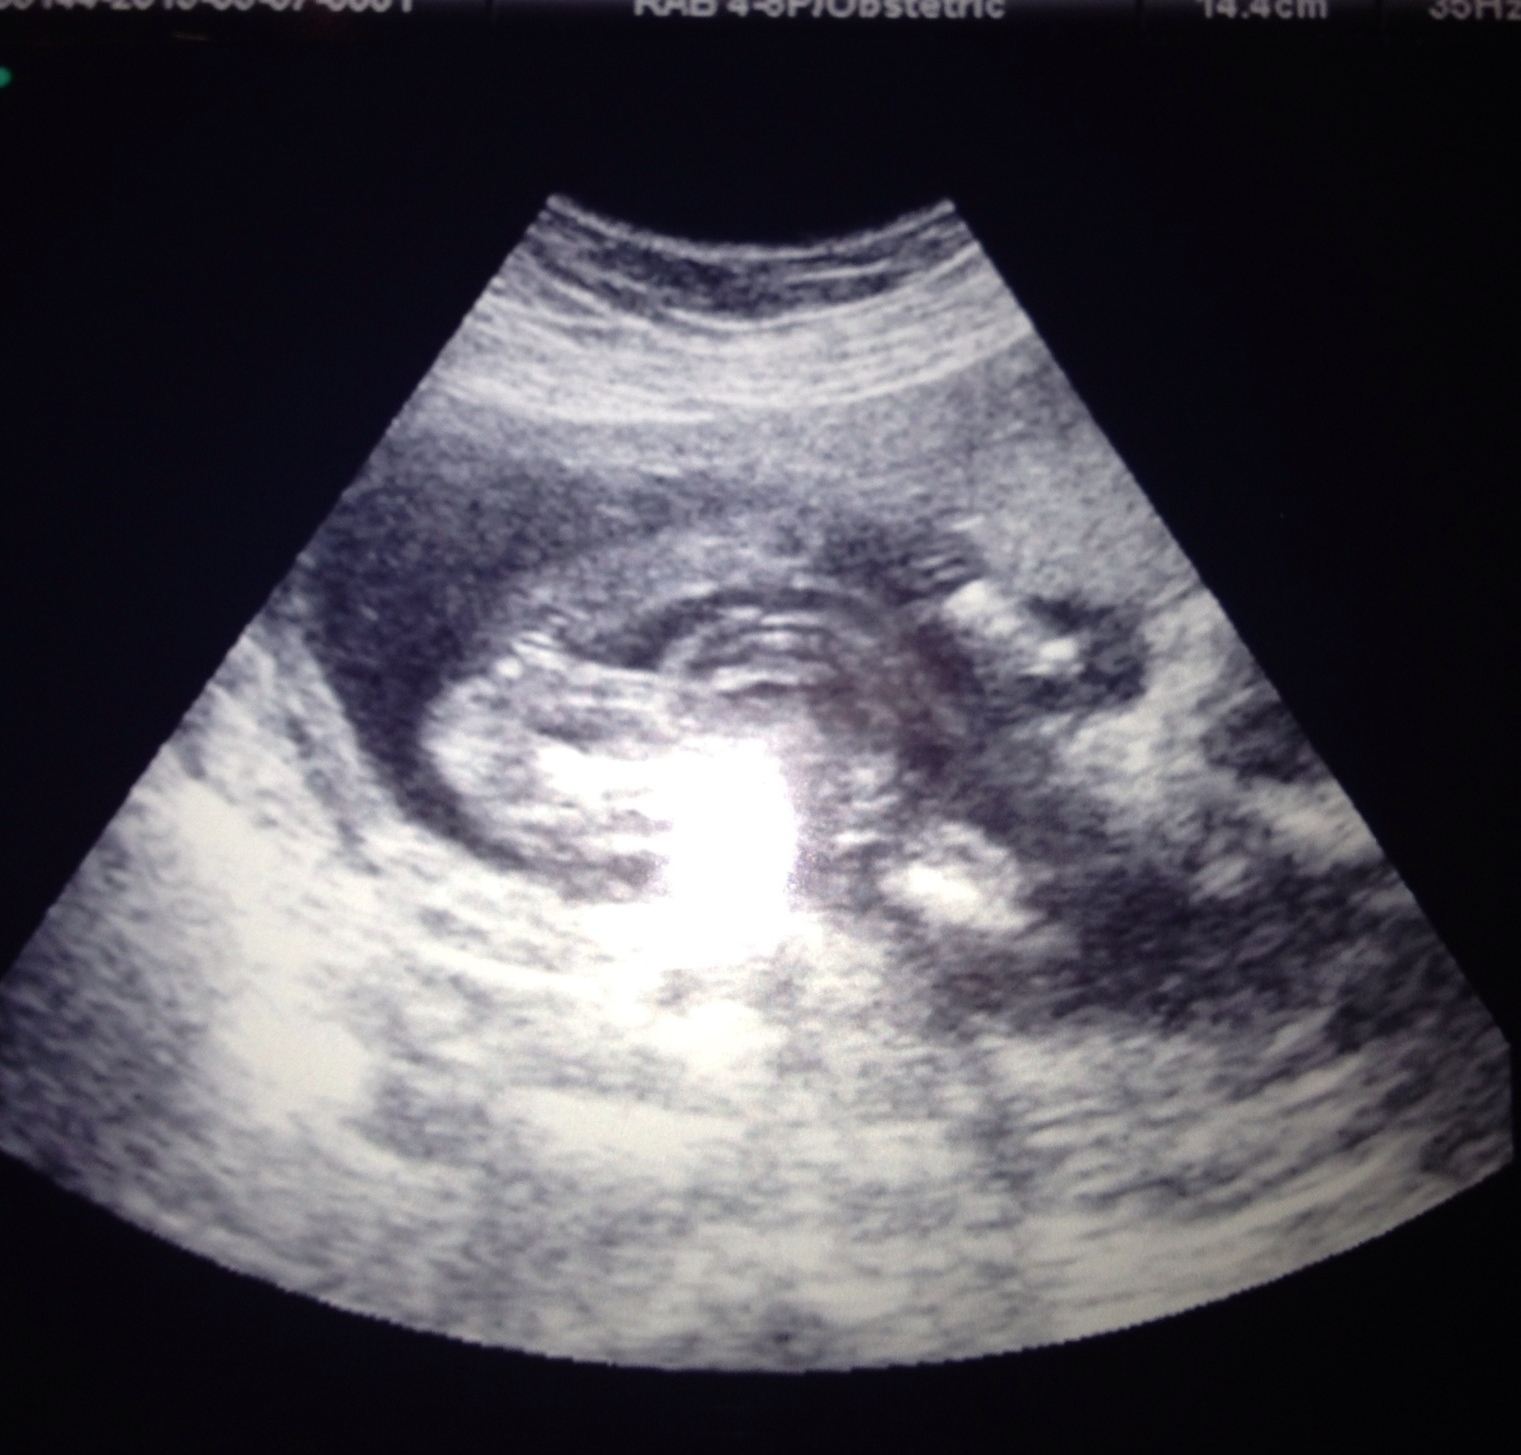

15.5 weeks